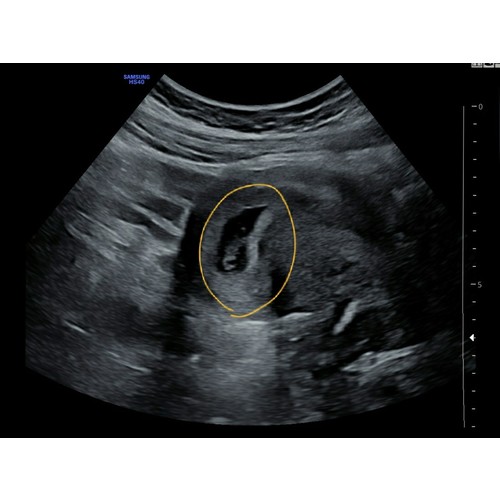

Pff dat is heel naar om mee te maken! Ik snap dat je het nu extra spannend vindt. Dit was onze echo met 7 weken. Links de dooierzak en rechts de baby.